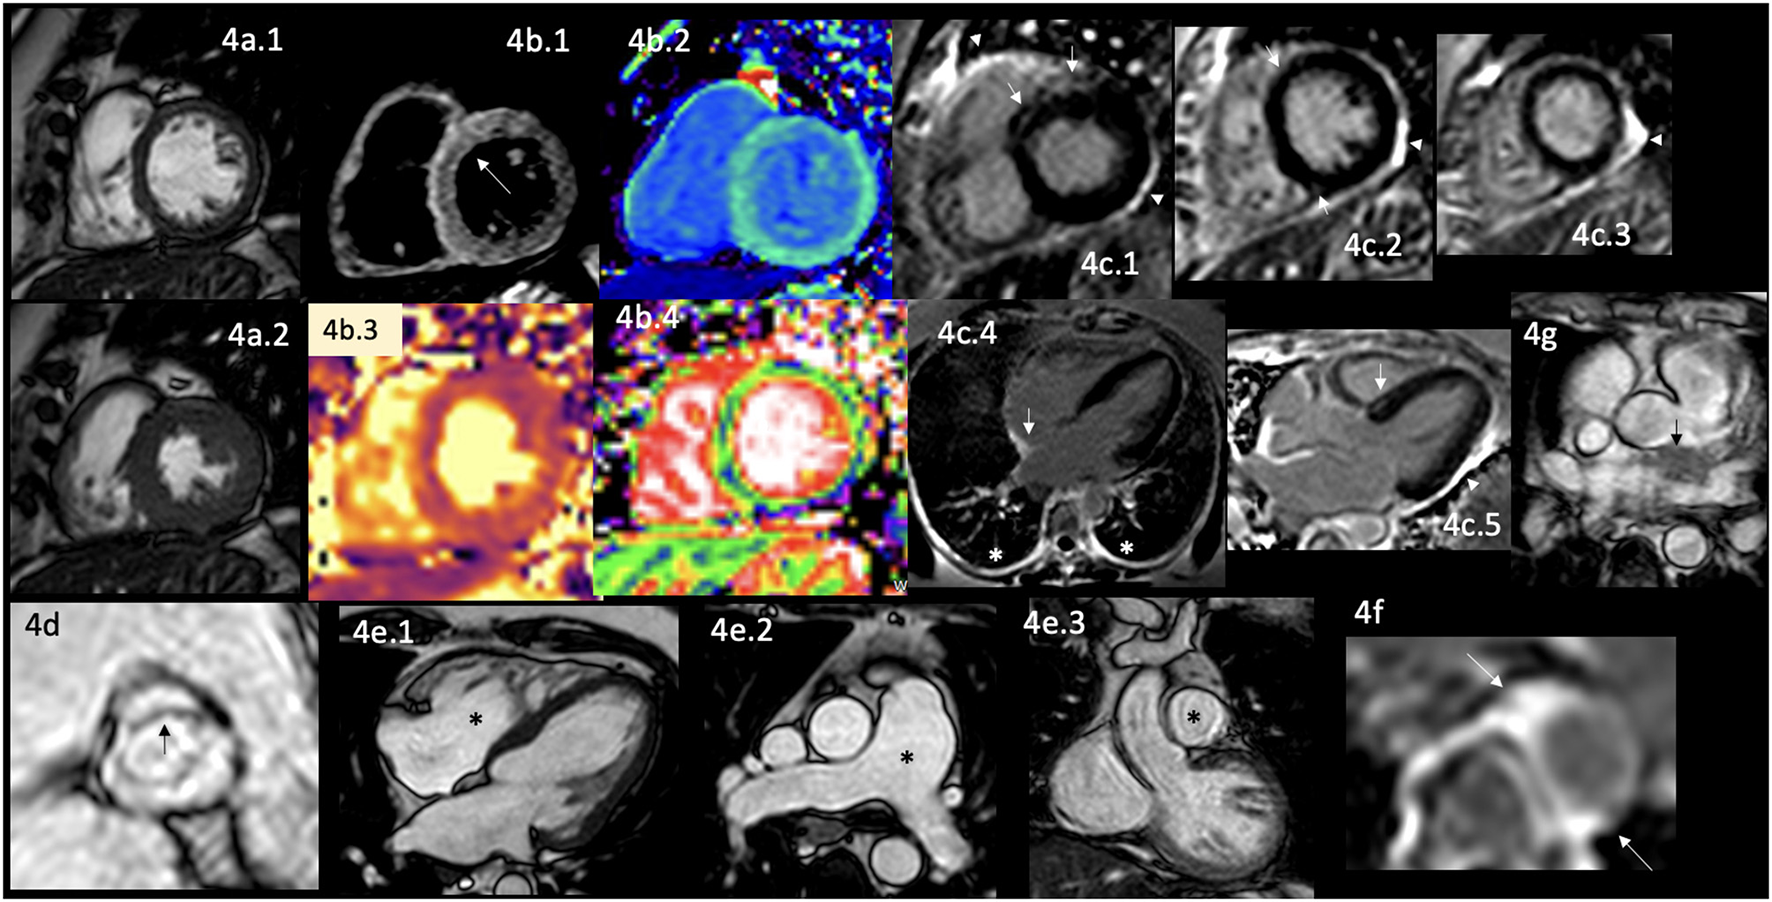

Figure 4

CMR findings in AR. A panel figure demonstrates varying findings from a comprehensive CMR study at a 3.0 Tesla scanner of RA with PH and arrhythmias. (a) SSFP sequence still cine images in short-axis view at the mid-ventricular level in end-diastole (a.1) and in end-systole (a.2) show normal global and regional left ventricular functions, mass, and wall thickness, LVEF 64% and moderately reduced systolic global RV function with global hypokinesia and mild hypertrophy (RV mass index 95 g/m2), RVEF 44%. (b.1) T2-W STIR sequence in short-axis view at a mid-ventricular level showing mildly increased signal intensity in the anterior, anteroseptal, and inferoseptal segments (arrow) with a myocardial/skeletal muscle ratio of 2.4 suggesting mild myocardial edema. (b.2) T1 mapping with a native T1 of 1,212 ms (normal), (b.3) T2 mapping with a T2 time of 42 msec (upper limit of normal) and (b.4) the ECV map corresponding to an elevated 52%. (c) LGE PSIR sequence. (c.1–3) Short-axis views at basal (c.1), mid (c.2), and apical (c.3) levels, and long-axis views in four-chambers (c.4) and three-chambers (c.5) projections. The arrows in these images show areas of focal fibrosis as midventricular LGE in the anteroseptal segment in (c.1,2) and the subepicardium of the anterior segment in (c.1) and subepicardial in the inferior segment in (c.2). (c.4) Shows LGE on the upper RA wall (arrow) and both-sided pleura (asterisks). (c.5) Shows mid-wall LGE on the anteroseptal segment. Pericardial LGE is shown in (c.1–3,5) (arrowheads), consistent with pericardial inflammation in the absence of pericardial effusion. (d) Zoomed still cine image in SSFP sequence of the aortic valve showing cusps thickening (arrow) with a mildly reduced valvular area (1.57 cm2). (e.1–3) SSFP sequence still cine images in long-axis 4-chambers view (e.1) showing RV enlargement (asterisks), (e.2) true axial view at great vessels level showing a mildly enlarged PA (asterisks) confirmed in the corresponding coronal view (e.3). (f) Zoom LGE PSIR image of the descending aorta showing wall artery enhancement (arrows). (g) SSFP sequence still cine images in the true axial view show an isointense tissue between the aortic root and the LA, probably of a granulomatous origin (arrow). CMR, cardiovascular magnetic resonance; RA, rheumatoid arthritis; SSFP, steady-state free precession; LVEF%, left ventricular ejection fraction; RVEF%, right ventricular ejection fraction; T2-W STIR, T2-weighted short-tau inversion recovery; ECV, extracellular volume; T1-W, T1-weighted; LGE, late gadolinium enhancement; PSIR, phase-sensitive inversion recovery; PA, pulmonary artery; LA, left atrium.

Therefore, many efforts to identify patients at risk of CVD have been made through different approaches. It has been demonstrated that patients have hidden or incipient damage during the AD diagnosis (110). Patients with RA have a broad spectrum of CV damage during their natural history, including the early presentation of left ventricular (LV) dysfunction (103) without other attributable causes. Early identification of cardiac abnormalities is crucial because it parallels other risk factors of this systemic disease (111–113), and the coexistence of CVD reduces survival (106, 114–116). It is also worrisome that in subclinical patients with RA, regularly evaluated with Echo, the LV global systolic function is reported as normal with diastolic dysfunction, frequently reported adequate to the age of the patient; however, when those same patients are evaluated with CMR (Figure 4a.1–2), it shows regional wall motion abnormalities with reduced circumferential strain at mid-ventricular level with LGE of non-coronary pattern often located in the inferolateral segment at basal and mid-ventricular levels (114–116).

Cardiac involvement in RA includes VHD in 9% of cases (128). The most commonly affected is the aortic valve, by thickening of its leaflets (Figure 4d) or frequently by producing stenosis (129, 130). Ischemic heart disease in 8% of cases (104, 128, 131), myocardial damage that usually remains subclinical (132, 133), and the development of HF of different degrees until reaching its congestive form in 10% of cases (104, 130, 134). Myocardial damage involves diverse causes, which are well described, including subclinical concentric LV hypertrophy, which is considered one of the earliest CV involvement (135–140), microvascular dysfunction, CAD, myocardial ischemia, myocarditis in 6% of cases (130, 141, 142) (Figure 4b.1–4), myocardial fibrosis (142, 143) (Figure 4c.1–5), dilated cardiomyopathy (141), pericardial effusion in 21% of cases (130), pericardial inflammation (Figure 4c.1–3,5), rhythm disturbances in 22% of patients of which 20% have conduction blockades (130), pleural effusion in 9% of cases (130), pleural inflammation (Figure 4c.4) and pulmonary fibrosis in 6% of cases (130). Great vessels are also involved; it is described as abnormal LGE, aortic compliance, and its pulse wave velocity (117, 144) reflecting aortic stiffness (Figure 4f).

The pathophysiological mechanisms are related to myocardial inflammation (Figure 4b.2,4), vascular remodeling, alterations in the extracellular matrix (Figure 4b.4), edema (Figure 4b.1,3), and myocardial injury demonstrated by circulating biomarkers, histology, and non-invasive imaging findings (145); premature atherosclerosis and the coexistence with other comorbidities as mentioned before. Interestingly, some areas of myocardial fibrosis match the cardiac conduction system in patients with intracardiac blockades (Figure 4c.4) that are not attributable to CAD or system degeneration.

RA patients are at increased risk for developing PH and right HF. The underlying mechanisms are interstitial lung disease, vasculitis, and chronic thromboembolic disease (146).

It has been proven that laboratory tests and specific inflammation imaging markers can predict the incidence of CV events (145, 148–153). Therefore a comprehensive CMR study is considered a valuable and minimally invasive diagnostic tool to assess cardiac involvement in asymptomatic and symptomatic RA patients (154); since it helps in the timely monitoring of the treatment response and early detection of the various structural and functional cardiac abnormalities (113), including the acceleration of atherosclerosis from the systemic inflammation (148, 155–158).

CMR can identify the indirect signs of PH in the same comprehensive study done to analyze the rest of the cardiac involvement of this disease (Figure 4e.1–3), constituting one of the complete non-invasive diagnostic modalities since it enables the evaluation of function and morphology of PA and RV (147). The findings are the gold standard measurements of RV function (147), systolic shift of the interventricular septum toward the LV, flow measurements, strain analysis with myocardial feature tracking, which can detect RV dysfunction even with normal RV ejection fraction (147), 4D-flow allowing more accurate and multilocation flow analysis simultaneously (159), LGE in RV which is associated with worse prognosis (147), T1 mapping that detects interstitial fibrosis even without evident LGE (147).

Interestingly, like in those patients with cardiac sarcoid, in some cases of RA, it is possible to visualize mediastinal extracardiac tissue (Figure 4g).